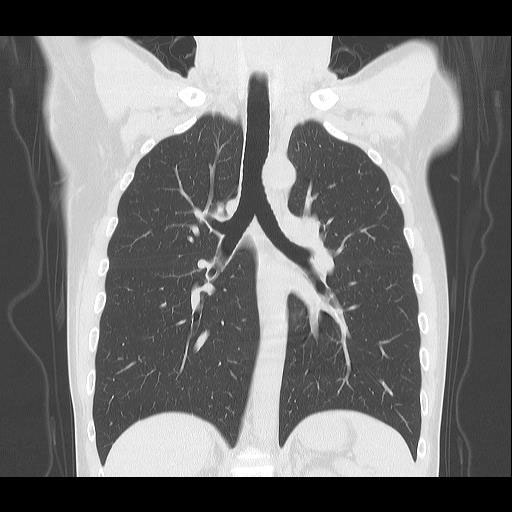

CT検査は様々な方向からX線を当て体内の水分や骨、空気など成分の違いを区別して画像を生成することで、レントゲン等では得ることができない臓器の状態を詳細に把握することが可能となり、小さい腫瘍などをより明確に映し出すことができます。

また、多角的に体内の断面図を得ることができるため立体的に構造を理解することが可能になり、病変の位置や広がりをより詳細に判断することが可能になります。